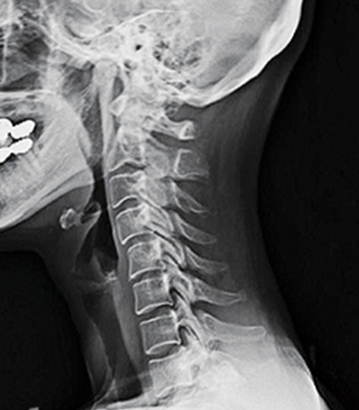

또한, 경추 전만 역전 또는 역 만곡이라 불리는 현상도 있는데, 이는 목의 만곡에 있는 척추뼈가 잘못된 방향으로 구부러져 전만보다 후만증이 더 심해지는 것을 의미합니다.

경추 전만증의 역전의 원인에는 자세 문제, 사고, 부상(과용 부상), 척추 측만증 및 골다공증과 같은 근본적인 척추 상태가 포함될 수 있습니다.